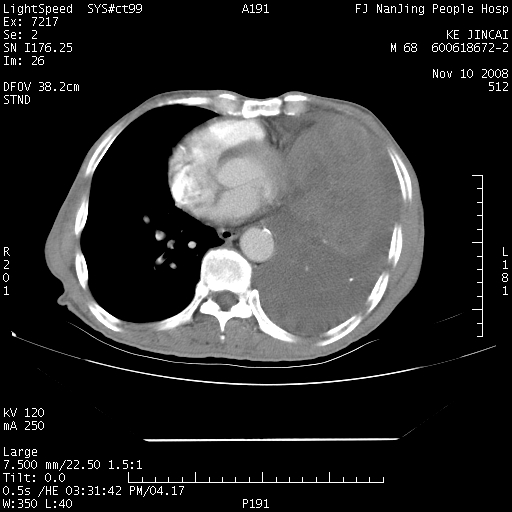

是个很有看头的病例,咋人气那么不旺?没多少人兴趣呢?这个病例几大怪:1   恶性肿瘤侵犯心肌左房怪,心肌一般不会被恶性肿瘤侵犯吧?2   左下肺均匀实变怪,内无含气,有别一般不张实变,含气肺泡完全为液体取代,而非一般不张实变的肺萎陷,冷不丁还以为是肿大的脾脏3   肿瘤本身怪,像tb肺不张4   这么有看头的病例没人气怪。呵呵。

左肺恶性肿瘤侵犯肺动脉,左心房内瘤栓,胸膜转移。

左肺恶性肿瘤侵犯肺动脉,左心房内瘤栓,胸膜转移,少见,学习了。